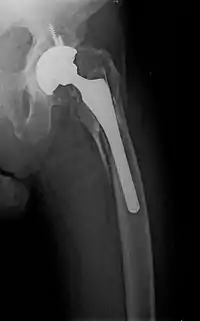

- Periprosthetic fracture – a fracture at the point of mechanical weakness at the end of an implant.

Surgical methods of treating fractures have their own risks and benefits, but usually, surgery is performed only if conservative treatment has failed, is very likely to fail, or is likely to result in a poor functional outcome.[39] With some fractures such as hip fractures (usually caused by osteoporosis), surgery is offered routinely because non-operative treatment results in prolonged immobilisation, which commonly results in complications including chest infections, pressure sores, deconditioning, deep vein thrombosis (DVT), and pulmonary embolism, which are more dangerous than surgery.[40] When a joint surface is damaged by a fracture, surgery is also commonly recommended to make an accurate anatomical reduction and restore the smoothness of the joint.

Occasionally, bone grafting is used to treat a fracture.[41]

Sometimes bones are reinforced with metal.[42] These implants must be designed and installed with care. Stress shielding occurs when plates or screws carry too large of a portion of the bone's load, causing atrophy. This problem is reduced, but not eliminated, by the use of low-modulus materials, including titanium and its alloys. The heat generated by the friction of installing hardware can accumulate easily and damage bone tissue, reducing the strength of the connections. If dissimilar metals are installed in contact with one another (i.e., a titanium plate with cobalt-chromium alloy or stainless steel screws), galvanic corrosion will result. The metal ions produced can damage the bone locally and may cause systemic effects as well.